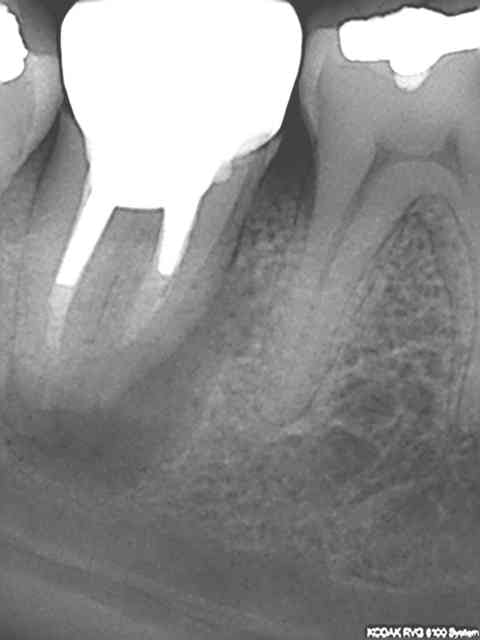

> @Chicot29: Tes endos sont superbes. Ce type de travail n'a aucune valeur pour

> santeclair et les autres guignols. Il n'y a que le prix, le prix, le prix. Tout

> le discours sur la qualité et le respect des normes de bonne pratique est de

> l'enfumage. Le but c'est de baisser le prix UN POINT C'EST TOUT. Il y a un

Ca c'était le cas de 14 h, voici le cas de 11h plus délicat. On verra ce que ca donne dans le temps ( finition au R40). C'est un peu creux en ce moment, heureusement qu'il y a des traitements réalisés conformément aux données acquises de la science à reprendre !)))))